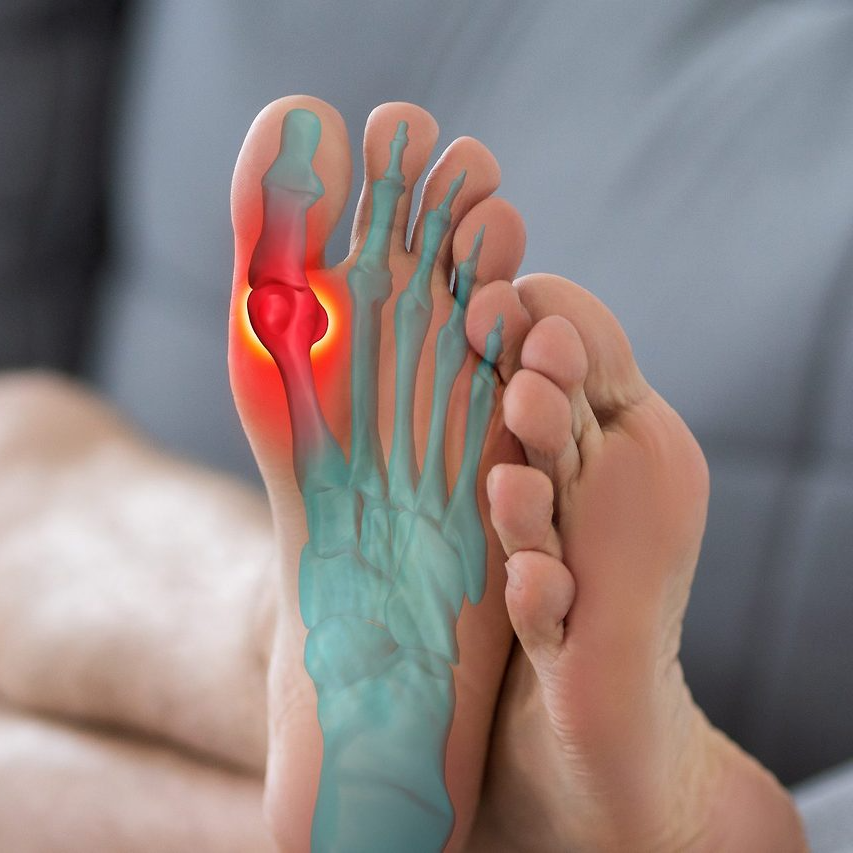

새끼발가락 골절의 주요 원인과 증상

일상생활에서 가장 흔한 골절 부위 중 하나가 바로 새끼발가락이다. 작은 부위지만 벽이나 가구 모서리에 부딪히거나, 무거운 물건이 떨어지는 충격으로 쉽게 골절이 발생할 수 있다.

특히 여름철 실내에서 맨발로 다니다가 발생하는 경우가 많다. 새끼발가락은 작은 뼈이지만 보행 시 균형을 잡는 역할을 하기 때문에 골절 시 통증이 크고 생활 불편이 심하다. 증상으로는 붓기, 피멍, 통증, 변형, 체중 부하 시 통증 악화 등이 있으며, 방치할 경우 잘못 붙어 변형이 남거나 보행 시 통증이 지속될 수 있다. 골절은 단순히 ‘금이 간 정도’의 피로골절부터 뼈가 완전히 어긋나는 개방성 골절까지 다양하다.